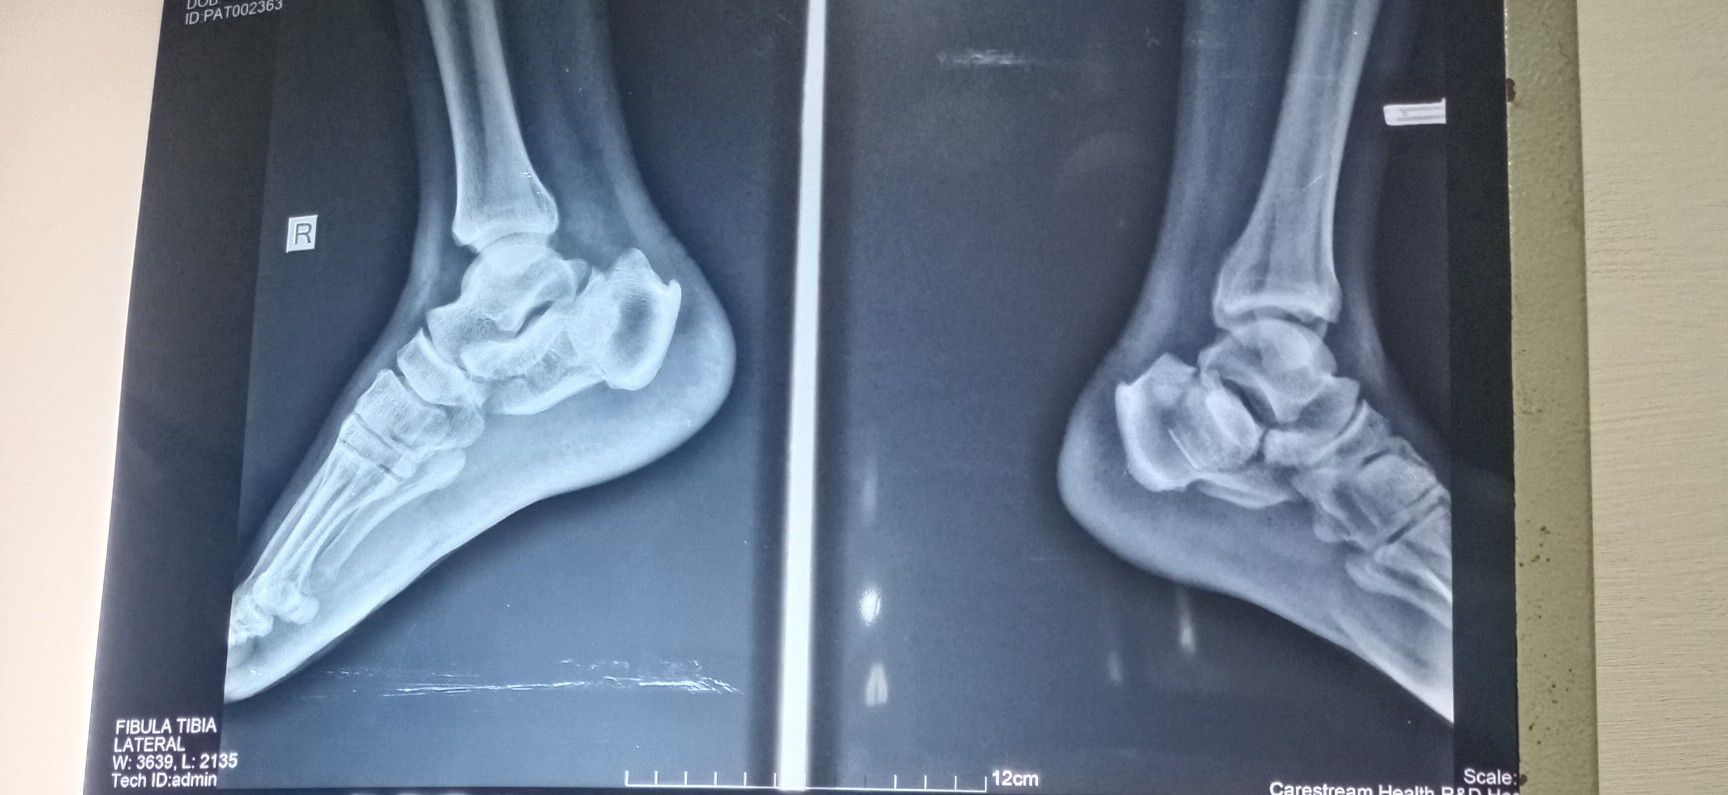

Heel fracture

Trauma

Fracture

Orthopedics

Calcaneus

Fallfromheightonheels